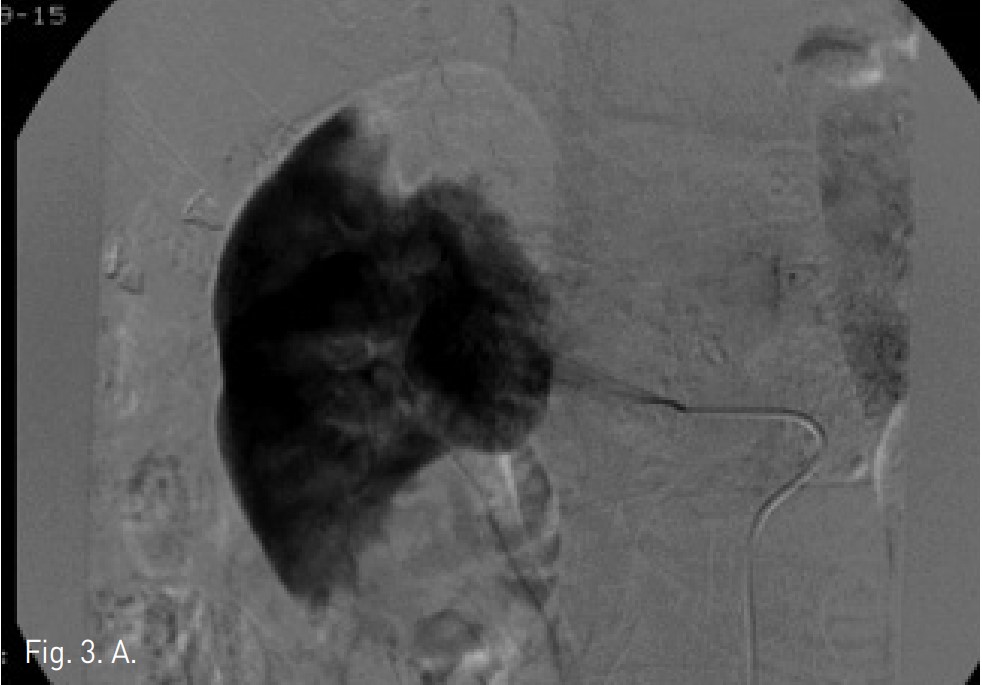

Fig. 3. A

Fig. 3. Renal angiography by supers election for middle segmental artery showed 2cm sized hypervascular RCC (A). After embolization by injection of mixture with ethanol 5mL and lipiodol 2mL, RCC was not detected on post-angiography (B).

5 Fr pigtail catheter를 right femoral artery를 통하여 suprarenal aorta에 삽입하고 혈관조영술을 시행하였음. 복부 CT에 대응되는 right middle segmental renal artery에서 supply 되는 약 2cm 크기의 과혈관성 종괴가 관찰됨(Fig. 3A). 5 Fr Yashiro catheter를 middle segmental renal artery에 삽입하고, 시행한 혈관조영술에서 종괴를 확인하고, 3 Fr microcatheter를 0.018 inch guide wire를 이용하여 co-axial technique으로 middle segmental artery의 branch를 superselection 한 후 시행한 혈관조영술에서 2개의 abnormal feeding artery를 확인하였음. Ethanol 5mL와 lipiodol 2mL를 혼합한 용액의 2/3를 이용하여 2개의 small vessel를 embolization하였음. 혈관조영술에서 right middle segmental artery의 종괴에 lipiodol